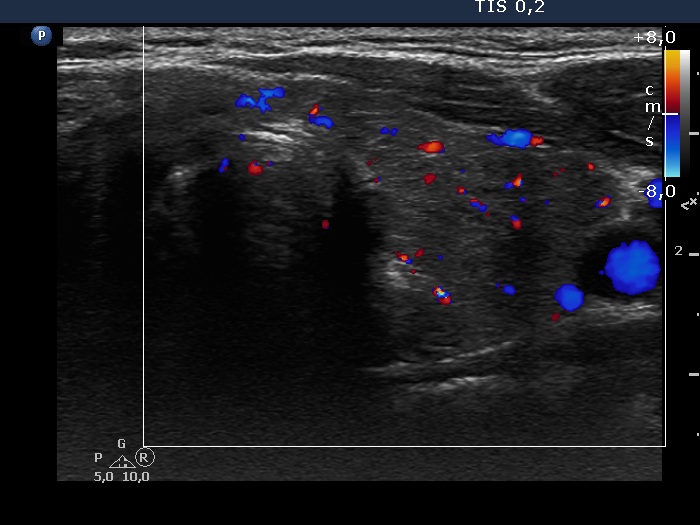

Consecutive patients with Hashimoto's thyroiditis - Case 39. (ultrasonographic picture 6)

Left lobe, horizontal view, color Doppler mode. The vascularization is a bit increased.